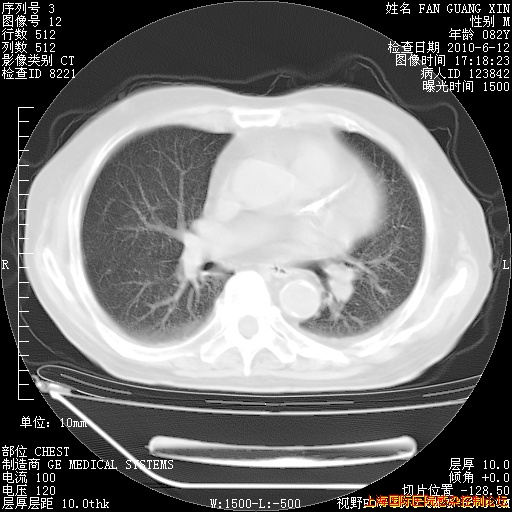

补发6月12日肺部CT肺窗

6月12日肺窗